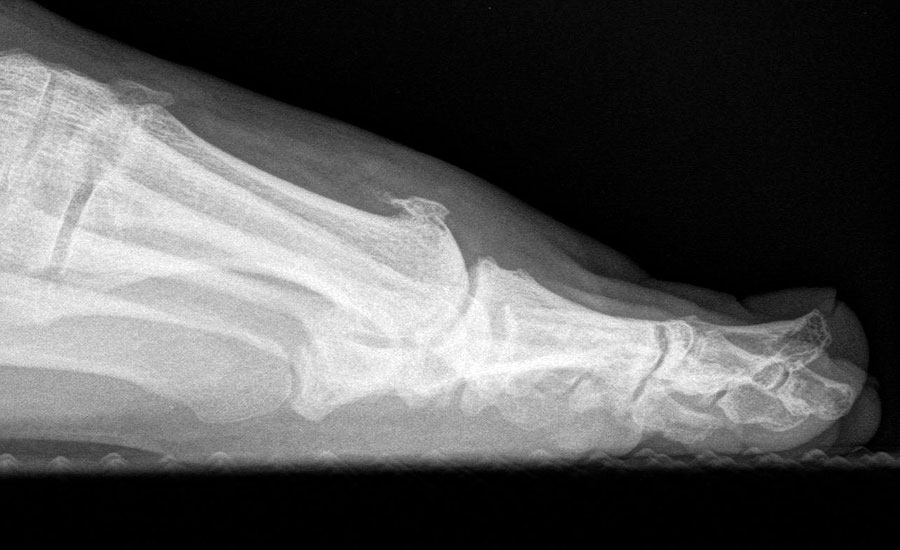

Klinisch zeigt sich stadienabhängig eine schmerzhafte Bewegungseinschränkung mit zunehmender Steifigkeit des Großzehengrundgelenkes. Vor allem die Einschränkung der Dorsalextension wird von den Patienten oft als unangenehm empfunden. Initial besteht eine bindegewebige Alteration im Gelenk, im weiteren Stadium treten Knorpeldegeneration und Begleitsynovialitis mit der Ausbildung von osteophytären Randanbauten auf. Klinische treten diese meist durch eine schmerzhafte dorsale Knochenkante in Erscheinung (Abbildung 1).

Im späten Stadium imponiert eine Gelenkblockierung durch freie Gelenkkörper. Während in den Anfangsstadien vor allem die dorsalen Anteile des Gelenks betroffen sind, betreffen die Veränderungen in den Fortgeschrittenen Stadien die gesamte Zirkumferenz einschließlich des Sesambeingleitlagers. Im Endstadium kommt es zu einer weitgehenden Ankylosierung des 1. Metatarsophalangealgelenks.